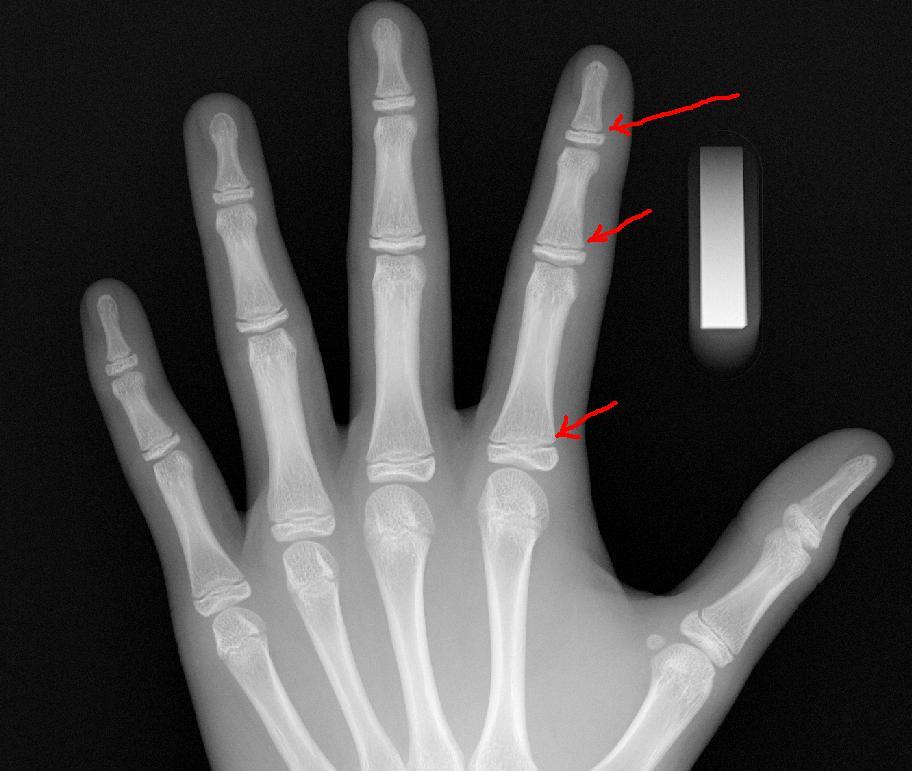

성장판 검사를 통해 성장판이 어느 정도 열려있고, 또 앞으로 얼마의 성장을 보일 것인가에 대한 예측도 중요하겠지만, 성장판 검사의 주 목적은 그 보다는 실제 아이의 나이와 뼈나이, 골연령과의 차이를 보기 위함이 더 큰 것입니다.

또한, 당장의 검사결과수치가 아니라 그 변화과정을 볼 수 있어야하기에 1년에 한 번, 또는 반년에 한 번, 경우에 따라서는 3달마다 검사를 반복하면서 골연령 진행속도를 보면서 성조숙증 여부를 체크할 수 있는 중요한 검사의 하나입니다.

성장판 검사에서 또 하나 중요한 것은 검사가 목적이 아닌, 판독과 판독결과를 가지고 아이의 건강을 상담하기 위한 것입니다.